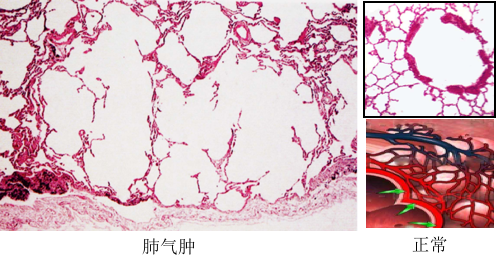

二、肺气肿

肺气肿(pulmonary emphysema)是指呼吸细支气管、肺泡管、肺泡囊、肺泡(图2-1)因肺组织弹性减弱而过度充气,呈永久性扩张,并伴有肺泡间隔破坏,致使肺容积增大的病理状态。其发病在45岁以后随年龄的增长而增加,是老年人的一种常见病和多发病。

图2-1

(2)肺泡性肺气肿的病理变化

图2-6

Ø 肺泡扩张,肺泡间隔变窄并断裂,相邻肺泡融合成较大的囊腔;

Ø 肺泡间隔内毛细血管床数量减少,间质内肺小动脉内膜纤维性增厚;

Ø 小支气管和细支气管可见慢性炎症改变。

肉眼观,气肿肺明显膨胀,边缘变钝,表面可见肋骨压痕,肺组织柔软而缺乏弹性,色灰白,切面肺组织呈蜂窝状,触之捻发音增强。